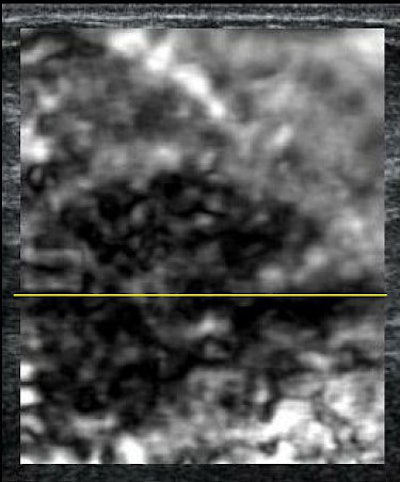

| Biopsy-proven IDC. Above, a conventional ultrasound image. Below, EI acquired at the same time with the same signals. The lesion in the elasticity image is much larger than the image in the conventional ultrasound, which is more likely to correspond to a malignant lesion. Images courtesy of RSNA. |

The lesions evaluated included infiltrating ductal carcinoma (IDC), ductal carcinoma in situ (DCIS), fibroadenomas, and cystic lesions. The average lesion size was 10 mm. Side-by-side, simultaneous sonographic images of the breast were produced in B-mode and with EI. The radiologist at each site measured the lesions and classified them as benign or malignant. Biopsy and its pathological results served as the reference standard.

In addition to differences in shading compared to normal tissue, EI depicted lesion stiffness or hardness, as well as changes in size. "Malignant lesions appear to be larger on the elastogram, while benign lesions appear to be smaller," Barr stated.